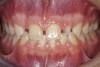

(1.) Initial presentation. Note midline shift to right, missing right lateral incisor, and diminutive left lateral incisor in crossbite.

Figure 1

A 14-year-old patient presented to the office with his mother (Figure 1). His chief complaint involved the large spaces between the teeth created by his missing right maxillary lateral incisor and his small left maxillary lateral incisor. He desired to replace the missing tooth with an implant and create a beautiful smile. Upon examination, he was found to have a class I canine and molar relationship, but because he had a tooth size/arch size discrepancy and space distal to the right central incisor, the remaining incisors had drifted to the right. The left maxillary lateral incisor was peg-shaped and in a cross bite position. Studies have shown a clear association between congenitally missing teeth and reduced tooth size.59-62 Because he was only 14 years old at the time and could not have implants placed until the cessation of growth (somewhere in the vicinity of 22 years old), he was sent to the orthodontist for alignment of the teeth.16,17 After 2 years of orthodontics, the appliances were removed, and his tooth coloration was improved using carbamide peroxide bleaching (Figure 2). Because some form of provisional needed to be placed until he was finished growing, a double-wing metal resin-bonded bridge was chosen. As discussed earlier, this is the ideal transitional prosthesis for patients that have congenitally missing maxillary lateral incisors. The benefits of this type of prosthesis include its ability to be removed and rebonded during the surgical phase of treatment and its ability to retain the roots in their proper position after orthodontic treatment.16 The final plan for the patient was to increase the width of the central and the maxillary left lateral incisor, utilizing porcelain laminate veneers to achieve the appropriate width/length ratio of 80%. A wax-up was created to idealize tooth size, a putty matrix was made from the wax-up to facilitate bonding of the incisors, and a non-precious, double-wing metal resin-bonded bridge was fabricated for lateral incisor replacement. Once the teeth were bonded to ideal size, the “Maryland Bridge” was fabricated from a polyvinyl arch impression with the newly bonded teeth (Figure 3). The metal frame was cast from a non-precious alloy to allow for fabrication of a very thin frame and to create a better surface for bonding. After sandblasting the internal aspect of the frame with CoJet™ silica (3M ESPE), accomplishing salinization, and executing cementation with a dual-cure resin cement, a fairly good adhesion to the frame was anticipated.29 The enamel surface was etched with phosphoric acid for 30 seconds, the primer (Single Bond Plus, 3M ESPE) was applied to both the internal surface of the sandblasted framework and the etched enamel, and the bridge was cemented with RelyX™ ARC (3M Espe) dual-cured resin cement (Figure 4 and Figure 5).